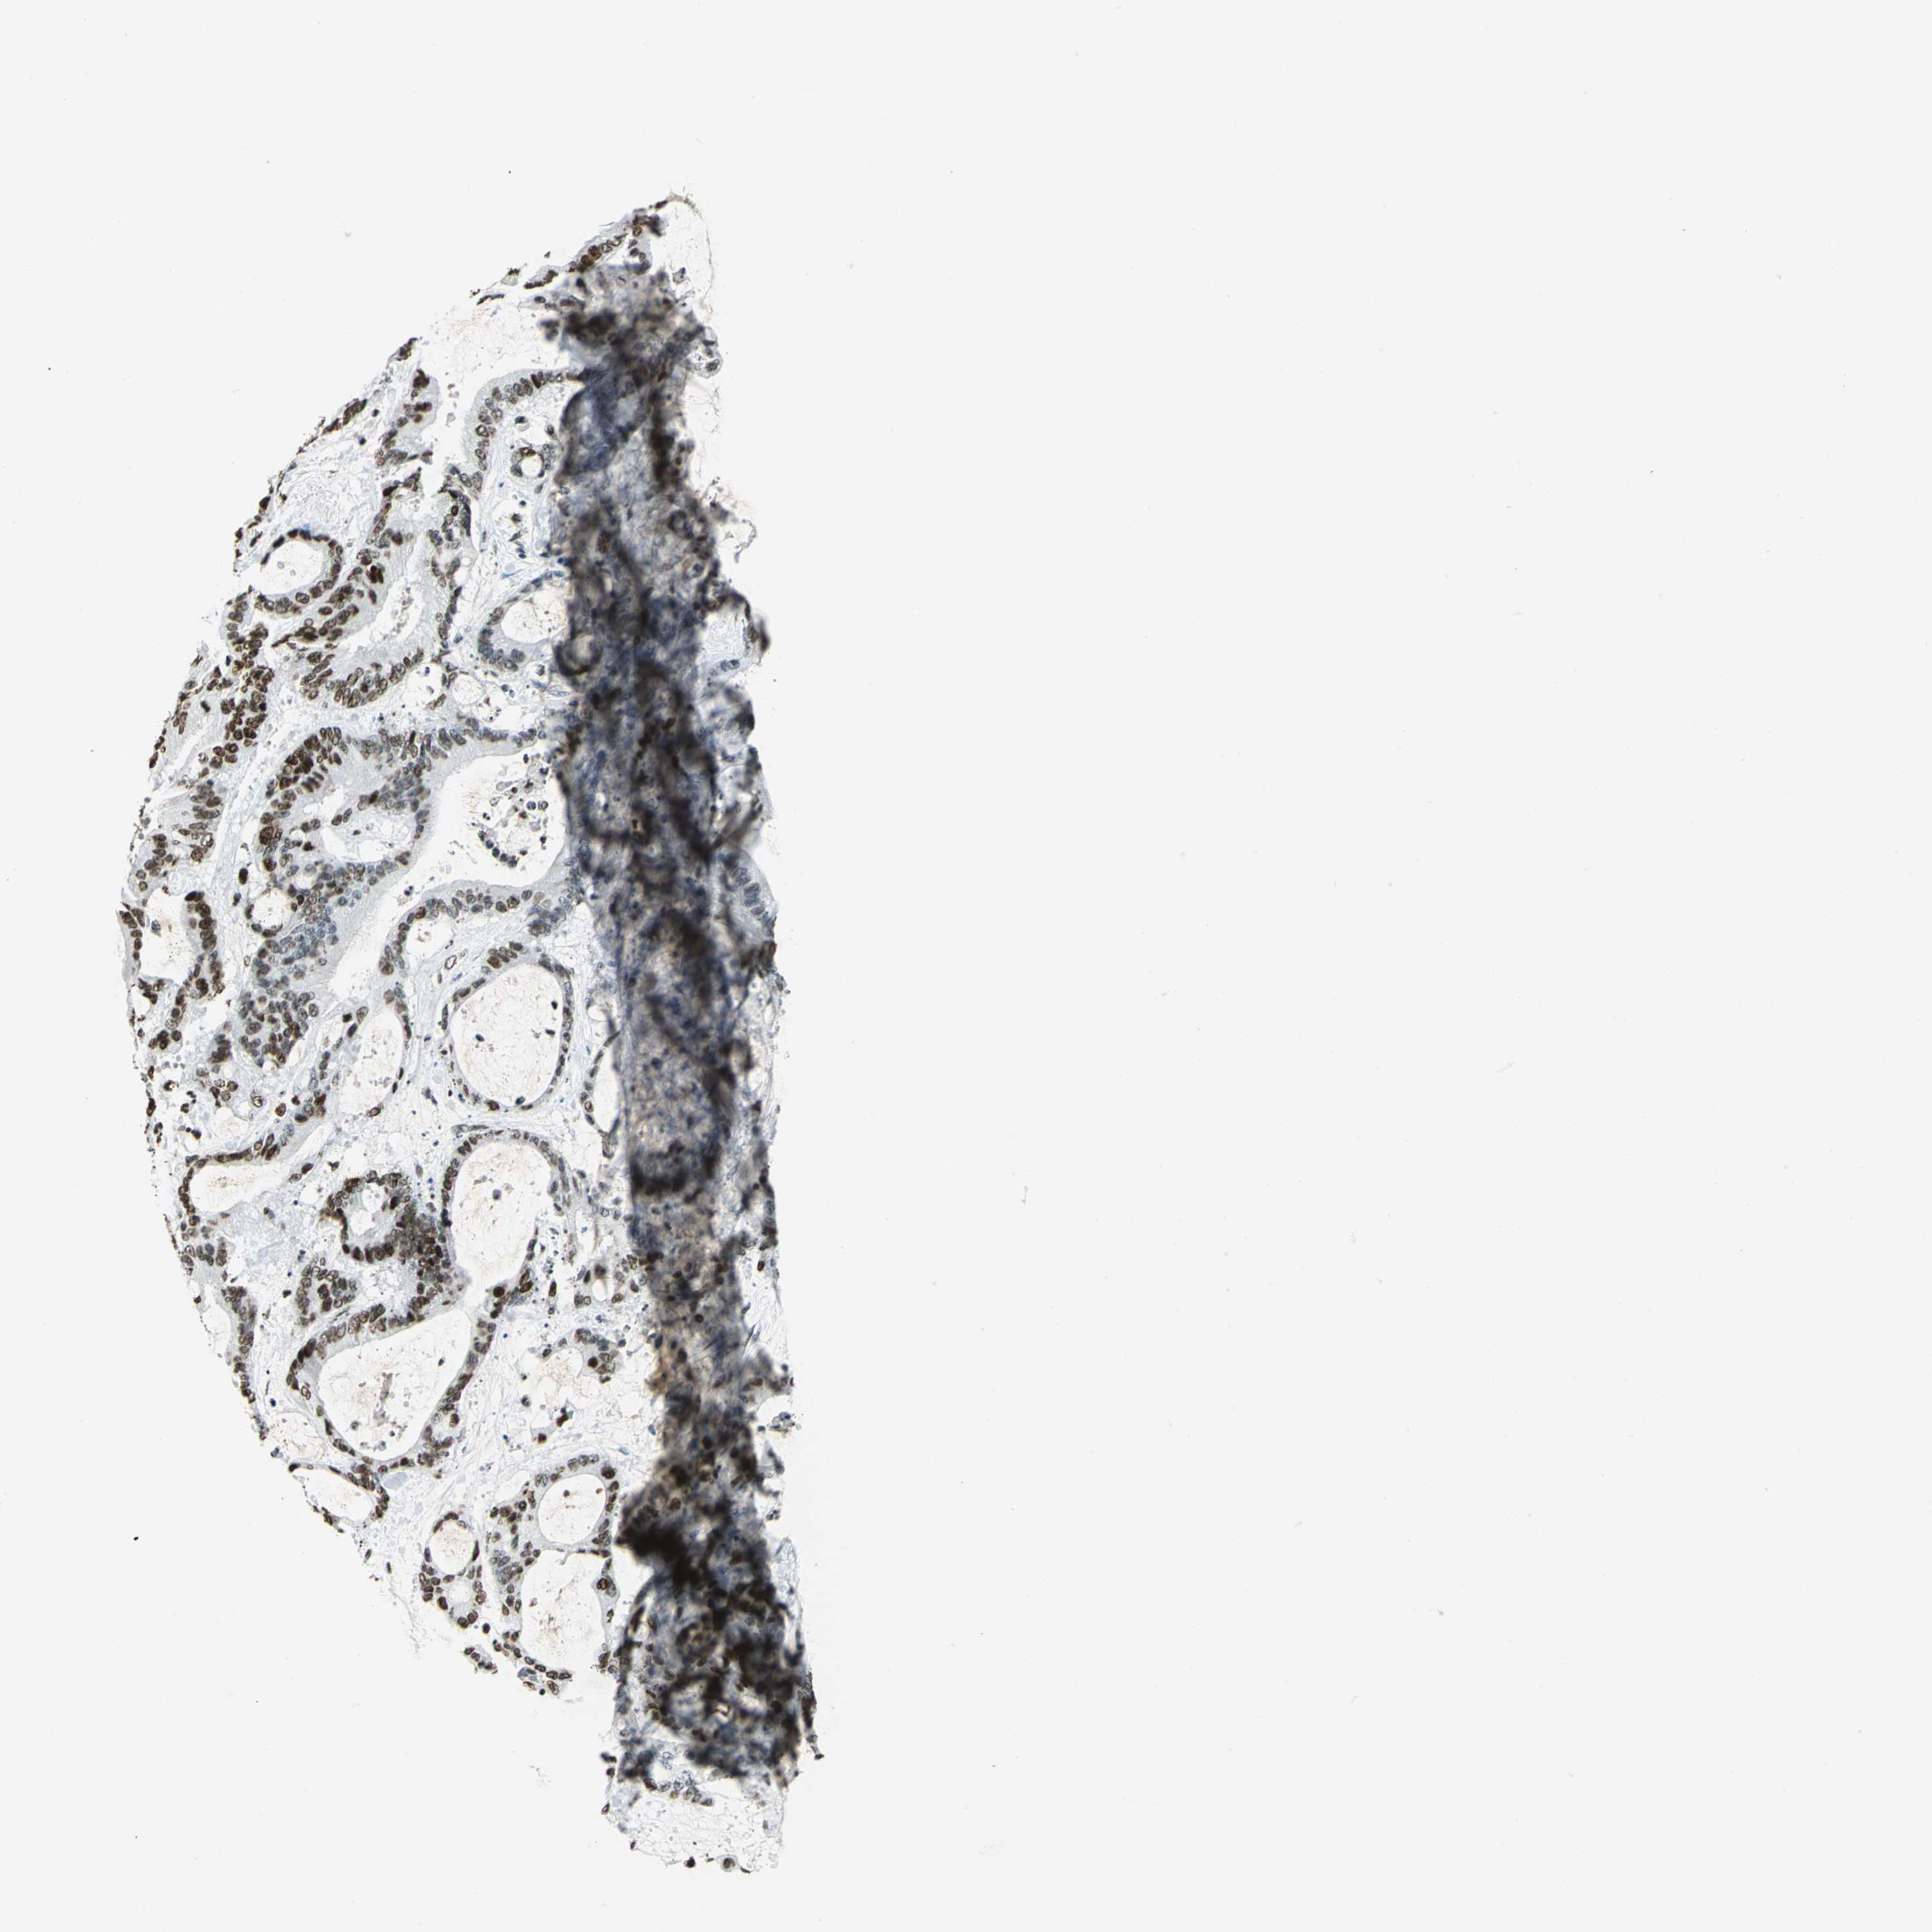

LIVER CANCER - Protein expressioni

A mouse-over function shows sample information and annotation data. Click on an image to view it in a full screen mode. Samples can be filtered based on level of antibody staining by selecting one or several of the following categories: high, medium, low and not detected. The assay and annotation is described here.

Note that samples used for immunohistochemistry by the Human Protein Atlas do not correspond to samples in the TCGA dataset.

Antibody stainingi

Antibody staining in the annotated cell types in the current human tissue is reported as not detected, low, medium, or high, based on conventional immunohistochemistry profiling in selected tissues. This score is based on the combination of the staining intensity and fraction of stained cells.

Each image is clickable and will lead to virtual microscopy that enables deeper exploration of all samples and also displays staining intensity scores, fraction scores and subcellular localization as well as patient and tissue information for each sample.

Antibody HPA004873

Antibody CAB004497

Staining

High

Medium

Low

Not detected

Intensity

Strong

Moderate

Weak

Negative

Quantity

>75%

75%-25%

<25%

None

Location

Nuclear

Cytoplasmic/membranous

Cytoplasmic/membranous,nuclear

Cholangiocarcinoma

Carcinoma, Hepatocellular, NOS